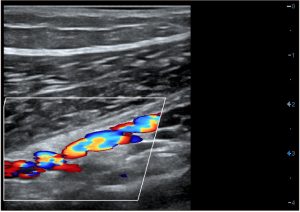

D — Заднебоковая перфорантная вена бедра.

- Варикозные вены проходят от латеральной или заднебоковой поверхности голени к бедру.

- Рефлюкс возникает в заднебоковой перфорантной вене бедра и чаще всего соединяется с глубокой бедренной веной, мышечными венами бедра и редко — с бедренной веной.